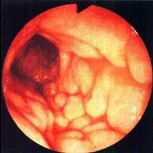

女性,农民,22岁,反复脓血便半年,左下腹压痛。

第1题,共4个问题

(单选题)肠镜检查如图,最可能的疾病为()。

A:溃疡性结肠炎

B:Crohn病

C:结肠癌

D:肠恶性淋巴瘤

E:肠结核